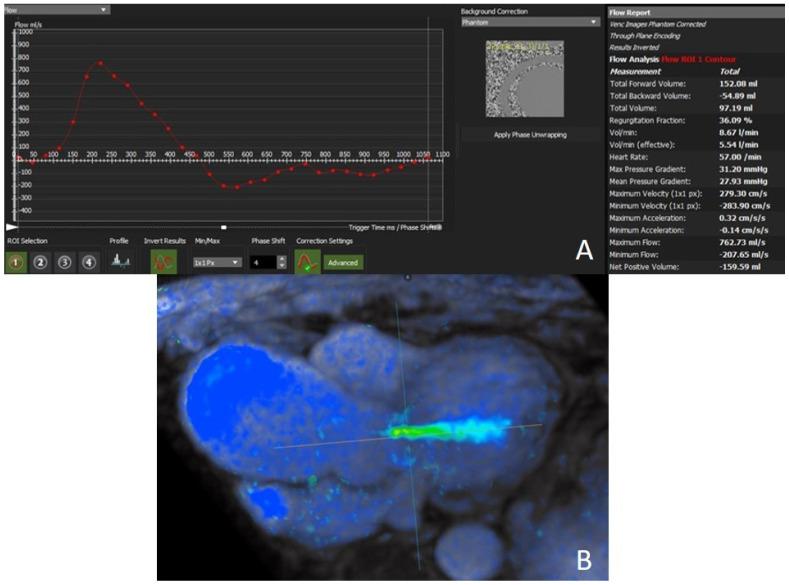

心脏磁共振在主动脉瓣狭窄和反流中的作用。

The Role of Cardiac Magnetic Resonance in Aortic Stenosis and Regurgitation.

Cardiac magnetic resonance (CMR) imaging is a well-set diagnostic technique for assessment of valvular heart diseases and is gaining ground in current clinical practice. It provides high-quality images without the administration of ionizing radiation and occasionally without the need of contrast agents. It offers the unique possibility of a comprehensive stand-alone assessment of the heart including biventricular function, left ventricle remodeling, myocardial fibrosis, and associated valvulopathies. CMR is the recognized reference for the quantification of ventricular volumes, mass, and function. A particular strength is the ability to quantify flow, especially with new techniques which allow accurate measurement of stenosis and regurgitation. Furthermore, tissue mapping enables the visualization and quantification of structural changes in the myocardium. In this way, CMR has the potential to yield important prognostic information predicting those patients who will progress to surgery and impact outcomes. In this review, the fundamentals of CMR in assessment of aortic valve diseases (AVD) are described, together with its strengths and weaknesses. This state-of-the-art review provides an updated overview of CMR potentials in all AVD issues, including valve anatomy, flow quantification, ventricular volumes and function, and tissue characterization.

摘要

心脏磁共振(CMR)成像对于评估心脏瓣膜病是一种成熟的诊断技术,并且在当前临床实践中越来越受到重视。它无需电离辐射即可提供高质量图像,偶尔也无需使用造影剂。它提供了对心脏进行全面独立评估的独特可能性,包括双心室功能、左心室重塑、心肌纤维化以及相关瓣膜病变。CMR是公认的心室容积、质量和功能量化的参考标准。其一个特别优势是能够量化血流,尤其是采用允许精确测量狭窄和反流的新技术时。此外,组织成像能够实现心肌结构变化的可视化和量化。通过这种方式,CMR有潜力产生重要的预后信息,预测哪些患者将进展至手术并影响预后。在本综述中,将描述CMR评估主动脉瓣疾病(AVD)的基本原理及其优缺点。这篇前沿综述提供了CMR在所有AVD问题方面潜力的最新概述,包括瓣膜解剖、血流量化、心室容积和功能以及组织特征。